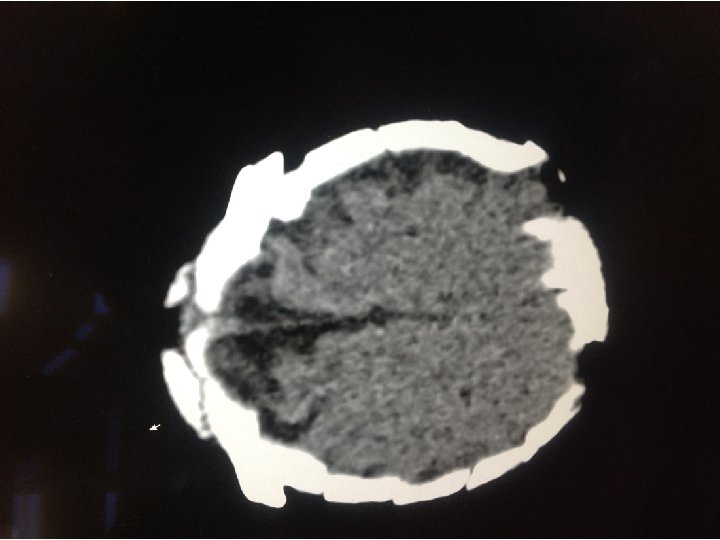

WORK UP • Basic labs • CBC, CMP, PT, INR, PTT • CT Head

SCAPHOCEPHALY • • • Male predominant Most common form Prominent occiput Broad forehead C-sections for cephalopelvic disproportion Does not produce increased ICP or hydrocephalus • Complications occur if two or more sutures close

SOOOO…. . ? • CT shows scaphocephaly, but normal ventricles. • No acute neurosurgical concerns • Primarily sent for nystagmus • Could the nystagmus be anything else?